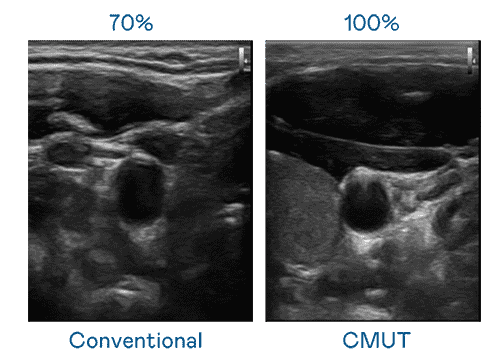

CMUT 技术是一种用电容式微机电元件来产生超音波讯号的技术。。与传统 PZT 压电式技术相比,,,,CMUT 频宽增加 30%,,更宽频的超音波讯号让影像解析度大幅提升,,,是实现高影像品质医疗超音波扫描、、促进精准医疗发展的关键技术。。

大频宽带来超清晰影像

超音波影像的解析度高低,,,首先取决于探头能发出的讯号频宽。。。汇旺支付 CMUT 可提供高清晰的超音波讯号,,,,提供高频宽、、、高灵敏度、、、影像纹理细节更高的超音波影像,,,协助医护人员缩短影像判读时间及利用精准的医疗影像进行诊断。。。